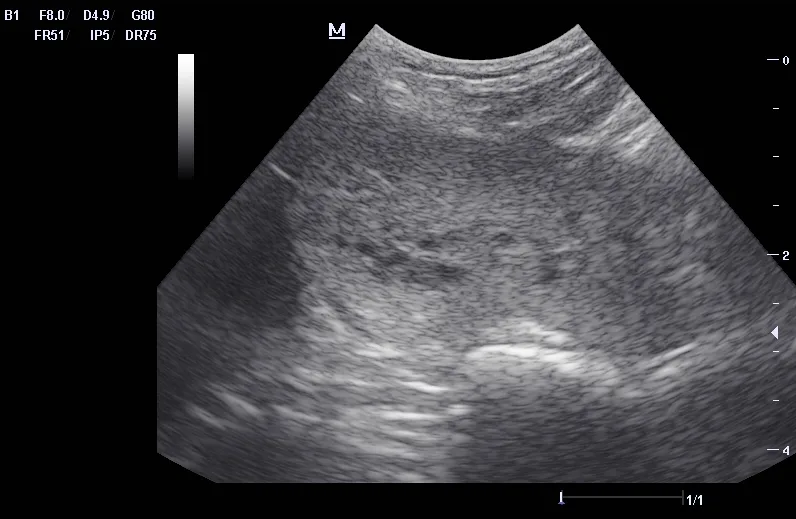

Ultrasound can be useful in evaluating the size, contour, and internal architecture of the prostate. A normal prostate appears homogeneous (Figure 1). The prostate becomes heteroechoic as a result of inflammation, hyperplasia, and neoplasia (Figure 2). The prostatic parenchyma can be focally or diffusely hypoechoic in cases of acute prostatitis or prostatic abscessation (Figure 3), as well as hyperechoic in cases of chronic prostatitis (Figure 4).

Ultrasound image of a canine prostate with small cysts.

FIGURE 2

Hyperplastic prostate with a heteroechoic appearance due to the presence of many small cysts